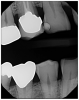

Enamel appears flat or thin on the incisal and occlusal surfaces. It may be localized, but usually is generalized. Small chips on the incisal edges may show radiographically along with broken teeth or restorations. Radiographically it would show widening of the periodontal ligament and bone resorption due to trauma enforced by the grinding.4 Pulpal necrosis may be visible (Figure 6 and Figure 7).

Figure 6. Thin enamel, flat cusps and bone

resorption.

Figure 6

Figure 7. Thin enamel and flat mandibular cusps with widening of the periodontal ligament on tooth #13.

Figure 7

Figure 8. Night guard.